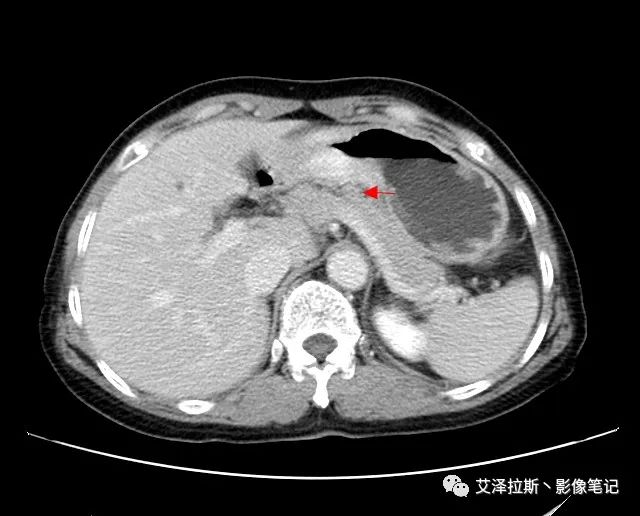

【影像所見】 胃竇部狹窄,胃壁環形增厚,小彎側見一巨大潰瘍,周圍伴“環堤征”,漿膜面不完整,胃周脂肪見網格狀條索影,病灶與肝臟左葉、胰腺鉤突脂肪間隙消失,增強掃描病灶明顯強化。引流區內約15個區域淋巴結受累。

【診斷意見】 胃竇部胃癌(T4N3期) 該病例腫塊突破漿膜層,與肝臟左葉、胰腺鉤突分界不清,脂肪界面消失,定為T4期; 受累及的淋巴結為15個區域,定為N3; 有無遠處轉移尚不明確,所以M期暫時無法確定。